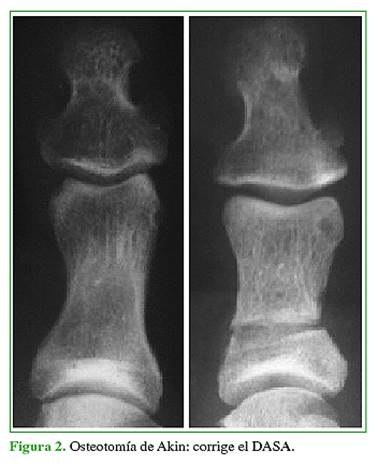

En mayoría de los casos, se recurre a las osteotomías para tratar el hallux valgus. En 1925, Akin13 describió un procedimiento para el hallux valgus que incluía la resección de la exostosis medial del primer metatarsiano, una osteotomía de resección en cuña de base medial en la base de la falange proximal del hallux y la liberación lateral del tendón abductor. Esta osteotomía falángica se popularizó como osteotomía de Akin, y fue descrita en la base de la falange proximal del hallux para la corrección del DASA (distal articular set angle) (Figura 2). Una variación de la osteotomía de Akin consiste en realizarla a nivel distal para corregir el hallux valgus IF (Figura 3). Se lleva a cabo en forma percutánea con técnica mínimamente invasiva.